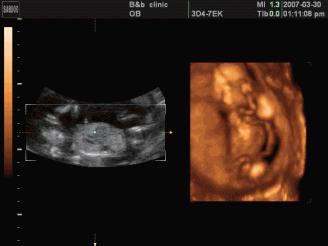

●三维彩超

是立体动态显示的彩色多普勒超声诊断仪,可以进行胎儿头面部立体成像,可显示眼、鼻、口、下颌等状态,协助医生直接对胎儿先天畸形进行诊断,价格比普通彩超价格贵。